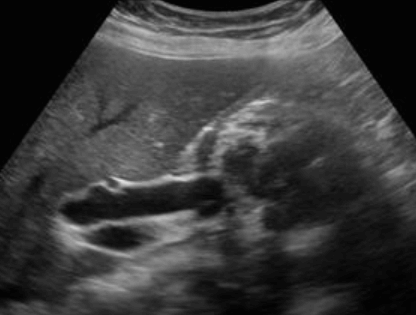

Choledocholithiasis US finding

- 총담관 내에 후방음향음영을 동반한 강한 에코가 관찰된다.

- 총담관의 확장 소견이 보인다. ( 7mm 이상)

- 담석이 관찰되지 않고 간외, 간내담관의 확장소견을 시사하는 엽총징후(shotgun sign)이나 평행관 징후(parallel channel sign)가 관찰되기도 한다.

- 엽총징후(shotgun sign): 간외 담관이 확장되어 간외 담관과 문맥이 이웃해 관찰된다.

- 평행관 징후(parallel channel sign): 간내 담관이 확장되어 인접하고 있는 문맥과 나란히 2개의 관상구조로 나타난다.